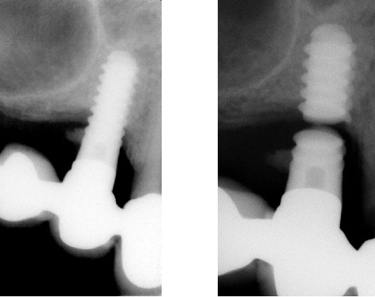

Fractura del implante

La fractura del implante es una ruptura del cuerpo del implante dental, generalmente debido a fuerzas excesivas o defectos en el material.

Los pacientes pueden notar dolor, movilidad del implante y, a veces, una sensación de fragmento suelto en la boca.

El tratamiento incluye la extracción del implante fracturado y la colocación de uno nuevo.